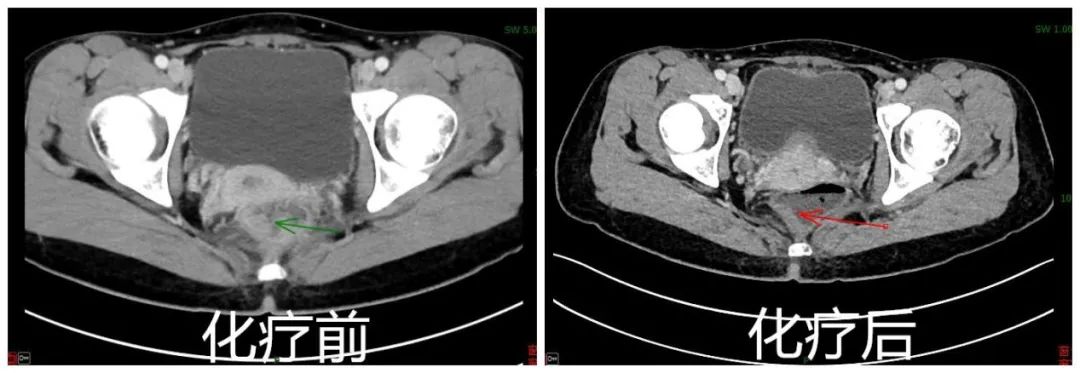

CT检查结果新辅助化疗前后对比

她找到赵医生寻求治疗。赵医生建议先做术前新辅助化疗,等便血之类的症状完全缓解,再次评估病情肿瘤临床分期降为cT1N1M0,肿瘤已经退缩为一个溃疡瘢痕。